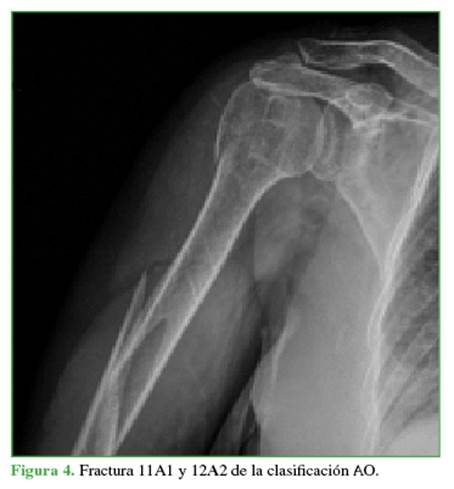

CASO CLÍNICO 2

Mujer de 68 años con fractura bifocal del húmero derecho Maresca tipo A2, 11A1 y 12A2 de la clasificación AO4 (Figura 4); traumatismo de seis días de evolución. Se indicó cirugía con la misma táctica quirúrgica detallada.

Se llegó a la consolidación clínico-radiológica a las cinco semanas. En el control alejado al año, se comprobó la restauración funcional del miembro con un puntaje funcional en la escala de Constant-Murley de 85. No se observaron complicaciones (Figura 5).